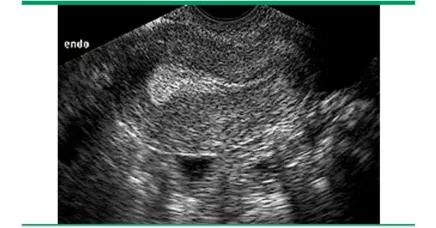

我们常常是用超声来检测月经周期中子宫内膜厚度及质地的变化,具体的测量方法是通过在矢状面的最大前后径水平,对子宫内膜与子宫肌层交界处的回声生成界面,进行测量而获得的厚度。

不同时期,B超下看到的子宫内膜的厚度影像也不同。

此后,在雌二醇分泌不断增加的影响下,内膜会增生持续整个卵泡期。这种增生在超声上表现为「三线征」,即子宫内膜表现为低回声,而中间和外基底层则表现为强回声亮线(如下图)。

到了卵泡期末期,测量的子宫内膜厚度为8-12mm之间[1]。在月经中期,子宫颈管可被黏液所扩张,表现为宫颈内的无回声带,这被认为是即将排卵的一个征象。

黄体期 — 排卵以后,「三线征」消失,取而代之的是一个10-14mm厚的强回声带。